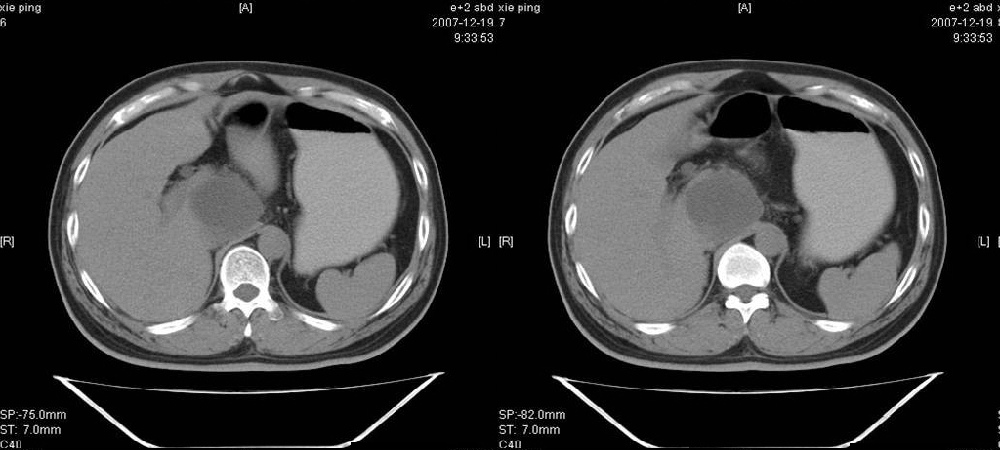

临床病史:患者,男,53岁,因反复上腹部饱胀不适2+月,在餐后或饥饿时明显,伴呃逆,无呕吐、呕血,无腹痛腹泻;2年前腹腔镜胆囊切除,否认肝炎、结核等病史。

胰腺头部低密度囊性病灶,边缘清楚,增强后囊壁略强化。考虑:胰头假性囊肿!

胰腺头部(或肝脏尾叶部)低密度囊性病灶,边缘清楚,增强后囊壁略强化。考虑:胰头假性囊肿. 或肝脏尾叶部囊肿。

考虑十二指肠憩室。从影像上看,病变位于下腔静脉前胰头后方十二指肠内侧,肝尾叶受压,说明病变来源于后腹膜;胰胆管成像胰管和胆道未见扩张,总胆管中段受压未显示,上下段正常,所以不考虑来源与于肝尾叶和总胆管的囊肿。考虑为十二指肠憩室或小网膜囊肿。

楼上高手,本例的确是一例十二指肠憩室.